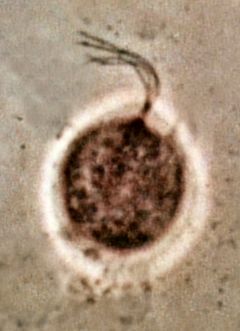

المشعرات البولية التناسلية (المشعرات المهبلية ) Trichomonus vaginalis

Trichomonas vaginalis is an anaerobic, flagellated protozoan, a form of microorganism. The parasitic microorganism is the causative agent of trichomoniasis, and is the most common pathogenic protozoan infection of humans in industrialized countries.[1] Infection rates between men and women are the same with women showing symptoms while infections in men are usually asymptomatic. Transmission takes place directly because the trophozoite does not have a cyst. The WHO has estimated that 180 million cases of infection are acquired annually worldwide. The estimates for North America alone are between 5 and 8 million new infections each year, with an estimated rate of asymptomatic cases as high as 50%.[2]. Usually treatment consists of metronidazole and tinidazole.[3]

- لها ثغير و ميزابة تلتف حول الخلية ،حركتها اهتزازية أبعادها 15_20 ميكرون .